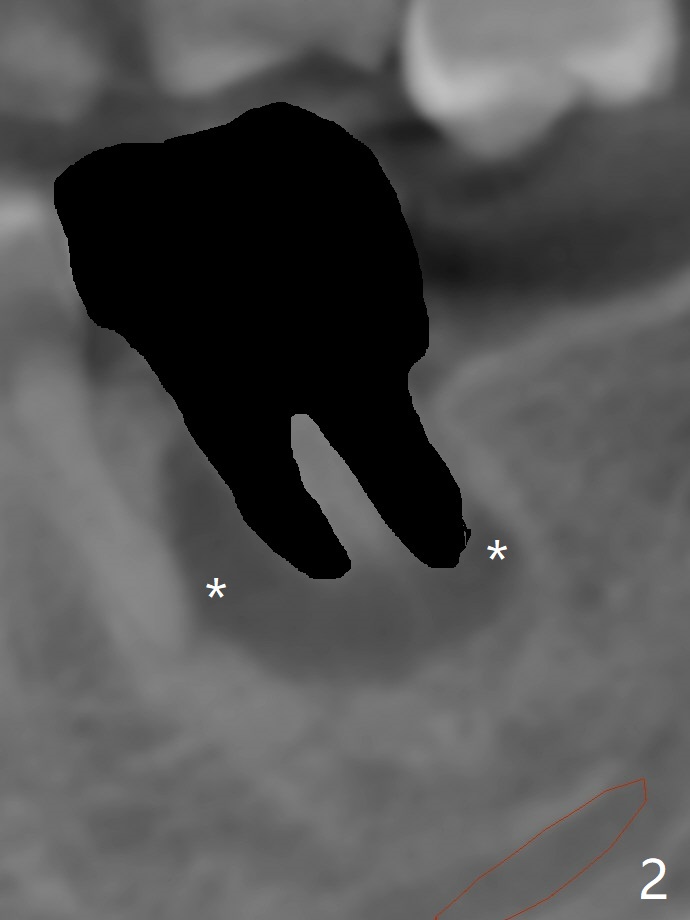

After placement of a 5x11 mm implant and cover screw at #18, allograft mixed with PRF (sticky bone) is placed in the peri-implant space, but it appears that bone density in the apical region (Fig.1 A) is lower than that in the coronal one (C) because of a constriction between the implant and the distal crest (*). Ideally the undercuts (Fig.2 *) of the extraction socket (black area) should be identified. Place bone graft in the undercuts (Fig.3 red circles) after osteotomy (white outlines) and before implant placement! A 4.5x1 mm temporary abutment is placed for an immediate provisional. The 2nd shortcoming of this case is that the implant is placed a little buccal. The papilla mesial to the immediate provisional (Fig.4 P) looks normal 4 days postop (no food impaction is expected when a final restoration is cemented). Additional acrylic (*) was placed to close a buccal gap when the provisional was seated with the temporary abutment. The patient reports loss of a piece of material in 4 days. It must be the additional acrylic, since it is absent 6 weeks postop (Fig.5). The provisional (Fig.5 P) looks wide, probably related to post-extraction gingiva and bone atrophy (Fig.6, 7 *). Bone graft (Fig.6 <) becomes a component of the gingival cuff. The provisional is re-trimmed for better oral hygiene. The gingival cuff is basically healthy 3.5 months postop, although the temporary abutment is loose and the implant is tender to rewinding and winding (Fig.8). The implant seems to remain non-osteointegrated 3.5 months postop (Fig.9). Although the bone density around the implant increases nearly 6 months postop (Fig.10), the implant remains tender when a 5x4(4) mm pair abutment is tightened. The healing abutment is reused. The bone density around the implant increases 11 months postop (Fig.11). Uncover is done with 5.5 mm profile drill. One month post uncover (12 months postop), the implant remains unstable (Fig.12). Prepare sticky bone x1. Make incision for exploration, including retightening the implant after Titanium brush and H2O2 Q-tip rubbing. If needed, a larger and shorter UF implant is a replacement (Fig.13). The implant is removed, cleaned with Titanium brushes and H2O2 in vitro and repositioned 12 months postop (Fig.14: arrow (gaps: post granulation tissue removal)). The gaps are regrafted with sticky bone and covered with PRF membrane and Cytoplast. Although the patient complains of severe pain the first 2-3 postop, the wound is apparently healing 12 days postop. The Cytoplast is exposed asymptomatic 5 weeks postop (Fig.16) and removed (Fig.17). The wound appears to have healed without loss of the bone graft (Fig.18).术后四个月伤口愈合,骨粉几乎没有丢失,有骨小梁形态(图十九:*)。切开,刮匙去骨,有一定硬度,即刻放置修复基台,完全就位(图二十),制备临时牙冠,牙周敷料固定组织瓣(没有缝线)。